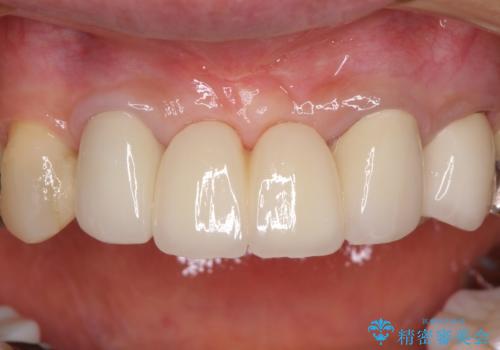

上唇小帯を切除したことで、ブリッジのダミー部分に触れて腫れていた歯肉は健全な状態になりました。

隙間もなくなったことで話す際の空気の漏れや、ものが挟まることもなくなりました。